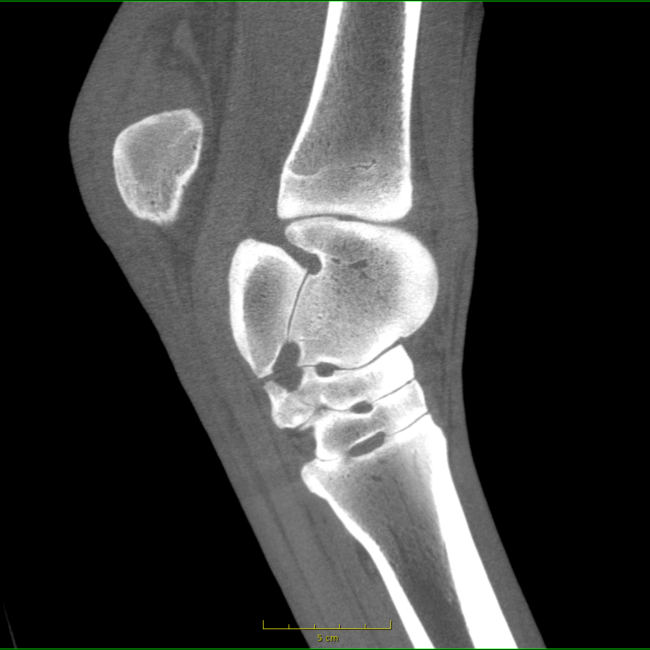

Our High Definition Volumetric Imaging (HDVI) technology represents the most advanced stage of Flat Panel CT technology. It offers exceptional diagnostic imaging for both hard and soft tissues, in diagnostic settings and intraoperative theaters. It is the gold standard for orthopedic applications.

Pegaso enhances safety and usability by enabling the scanning of a standing horse’s head, neck, and limbs.

Pegaso scans head, neck and limbs of the standing horse